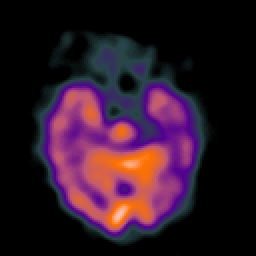

Alzheimer's disease: Perfusion SPECT -- Slice #16

[Home][Help][Clinical][Tour 1][Tour 2] Slice 16